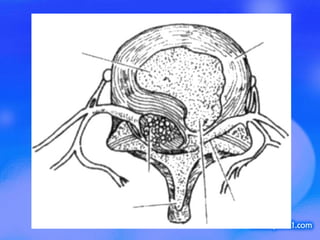

腰 1 椎—骶 1 椎分别有 5 个椎间盘 , 并有 5 对神经根自后方的椎间孔发出 . 椎骨 椎间盘和神经根结构图

椎间盘的结构和作用 结构 :  纤维环 髓核 软骨板 作用 :  弹性负重   缓冲振荡

椎间盘的上下观

椎间盘突出的基本分型 1  按突出部位分为 中央型  后外侧型  极外侧型